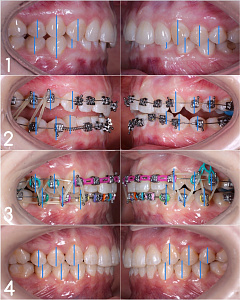

Гегиров Амир Артурович (@amir__ortodont)

Врач-ортодонт

#repost от @amir__ortodont

Была проведена полная фиксация брекетов на обе челюсти, установлены дуги и дополнительные элементы для запуска контролируемого перемещения зубов. Уже с первых месяцев лечения начинается работа над выравниванием зубных рядов, подготовкой места для правильного положения клыков и коррекцией прикуса.

В данном случае наблюдается выраженный дефицит места для клыков, поэтому лечение будет проходить поэтапно и с использованием дополнительной опоры. Каждый элемент системы работает на прогнозируемый и максимально эффективный результат.

Была проведена полная фиксация брекетов на обе челюсти, установлены дуги и дополнительные элементы для запуска контролируемого перемещения зубов. Уже с первых месяцев лечения начинается работа над выравниванием зубных рядов, подготовкой места для правильного положения клыков и коррекцией прикуса.

В данном случае наблюдается выраженный дефицит места для клыков, поэтому лечение будет проходить поэтапно и с использованием дополнительной опоры. Каждый элемент системы работает на прогнозируемый и максимально эффективный результат.